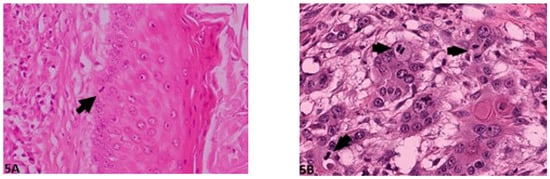

2.2.1. Invasive front Grading System (IFGS)

2.2.2. Tumor Cell Budding Grading System (TCBGS)

| Degree of keratinization | Highly keratinized (>50% cells) | Moderately keratinized (20–50% of cells) | Minimal keratinization (5–20% of cells) | No keratinization (0–5% of cells) |

| Pattern of invasion (bone or dermis) | Pushing, well-differentiated, infiltrating borders | Infiltrating, solid cords, bands and/or strands | Small groups/cords of infiltrating cells (n > 15) | Widespread cellular dissociation in small groups and/or in single cells (n < 15) |

| Host response | Marked | Moderate | Slight | None |

| Nuclear pleomorphism | Mild (<25% anaplasia) | Moderate (25–50% anaplasia) | Marked (50–75% anaplasia) | Extreme (75–100% anaplasia) |

| Mitosis HPF (40×) | 0–1 | 2–3 | 4–5 | >5 |

| Tumor Budding Activity/10 HPF | Score Value |

| No budding | 1 |

| <15 budding foci | 2 |

| ≥15 budding foci | 3 |

| Smallest cell nest size | |

| >15 cells | 1 |

| 5–15 cells | 2 |

| 2–4 cells | 3 |

| Single cell invasion | 4 |